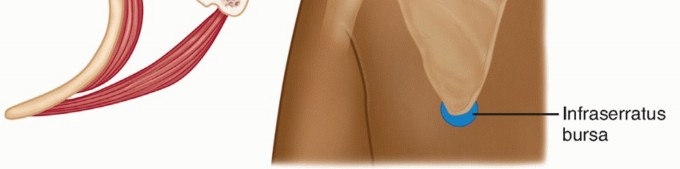

Osseous causes of snapping scapula syndrome are rare. These include scapular osteochondromas and exostoses (FIG 3*), anterior angulation of the scapula, scapular fracture, scapular tubercle of Luschka, skeletal abnormalities of the vertebrae (omovertebral bone), and abnormal angulations and tumors of the ribs.20,21,35

Several osseous anatomic variants on the ventral surface of the scapula have been implicated as a potential cause of snapping scapula syndrome.

The tubercle of Luschka is a ventral osseous prominence at the superomedial angle of the scapula, which was found in 3% of cadaveric specimens. A teres major tubercle was found in 43.2%, and a teres major process

was found in 6.8%.36

Osseous causes of snapping scapula syndrome are rare. These include scapular osteochondromas and exostoses (FIG 3*), anterior angulation of the scapula, scapular fracture, scapular tubercle of Luschka, skeletal abnormalities of the vertebrae (omovertebral bone), and abnormal angulations and tumors of the ribs.20,21,35

Several osseous anatomic variants on the ventral surface of the scapula have been implicated as a potential cause of snapping scapula syndrome.

The tubercle of Luschka is a ventral osseous prominence at the superomedial angle of the scapula, which was found in 3% of cadaveric specimens. A teres major tubercle was found in 43.2%, and a teres major process

was found in 6.8%.36

FIG 3 • An osteochondroma (arrow) of the superomedial angle of the scapula may, rarely, be the cause of snapping scapula syndrome.

FIG 3 • An osteochondroma (arrow) of the superomedial angle of the scapula may, rarely, be the cause of snapping scapula syndrome.